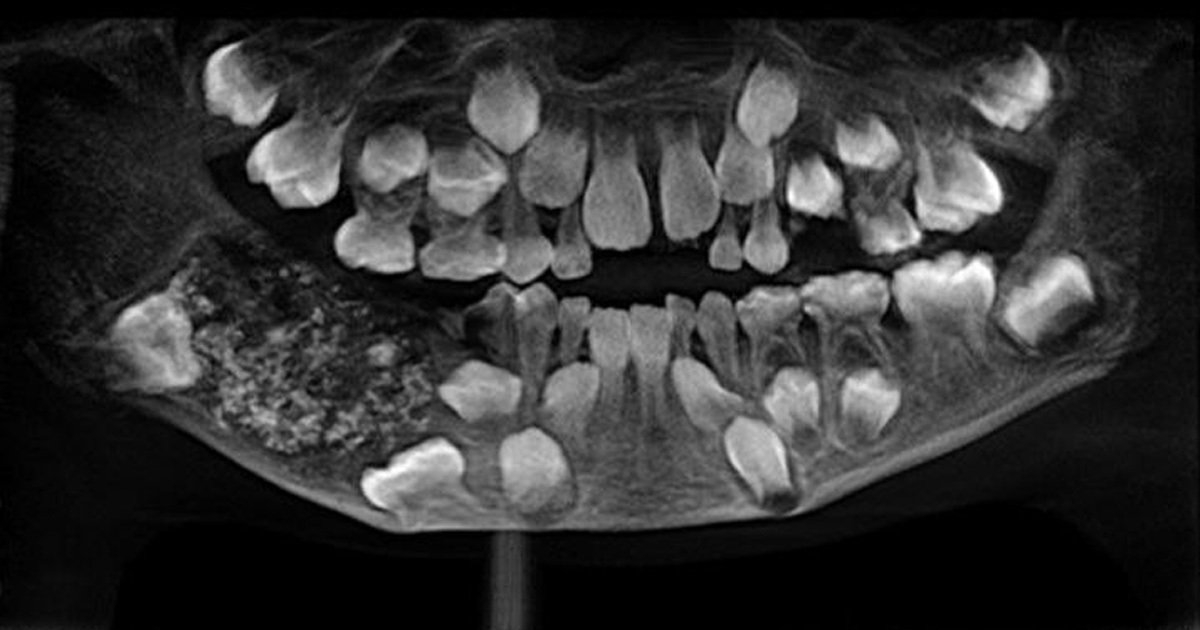

7歲男孩下顎長出「詭異肉包」 醫生一劃…驚見「526顆密集牙齒」